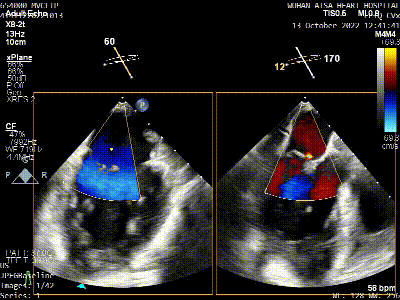

术前TEE评估

原发性二尖瓣反流(DMR),后叶P3区脱垂,反流程度4+,EROA 0.40cm2、RV 39ml;二尖瓣瓣口面积5.37cm²;二尖瓣前叶(A3)长度14.0mm,二尖瓣后叶长度(P3)长度12.2mm,脱垂宽度8.2mm,脱垂高度1.4mm;RA 2.9cm ,LA 3.6cm,左室射血分数LVEF56%,术前测量最大房间隔穿刺高度4.0cm